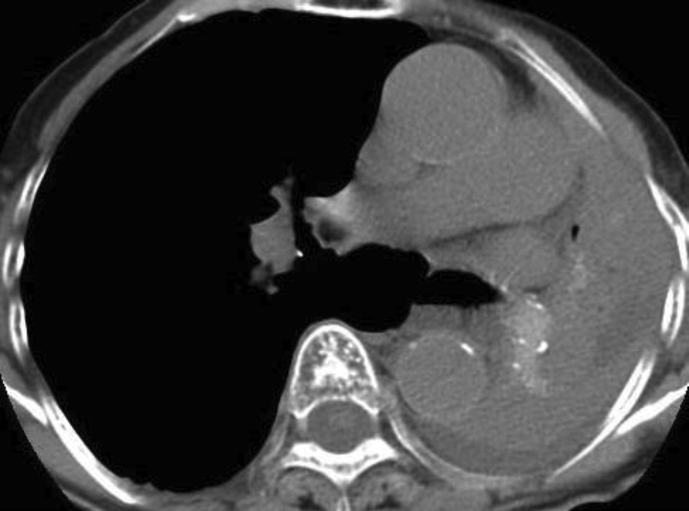

Upon examination, SpO2 was 89% at room air. Laboratory test showed elevated eosinophil count at 651/μL. Additionally, chest radiograph and computed tomography (CT) findings revealed complete collapse of the left lung with hyperattenuated mucoid (HAM) impaction (Fig. 2). Bronchoscopy showed a white, rubbery, thick mucus plug in the left main bronchus, which could not be removed by forceps or suction (Fig. 3). The findings on pathologic examination were eosinophilic infiltration without Charcot-Leyden crystals on Hematoxylin and Eosin stain and presence of fungal mycelium on Grocott stain. Culture of the small pieces of the mucus plug obtained during bronchoscopy yielded S. commune.

Fig. 2.

Chest computed tomography obtained upon admission shows complete collapse of the left lung with hyperattenuated mucoid impaction.